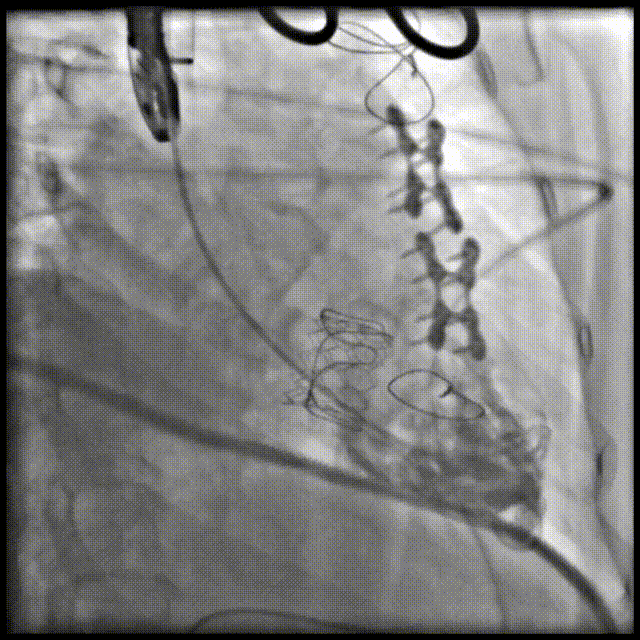

手术顺利,经右颈静脉入路成功植入27号Renato球扩式瓣中瓣。瓣膜植入位置理想,无瓣周漏及中央返流。经查阅现有资料,经颈静脉路径成功完成三尖瓣“瓣中瓣”治疗在国内尚属首例。

▲球扩三尖瓣 ▲右室造影